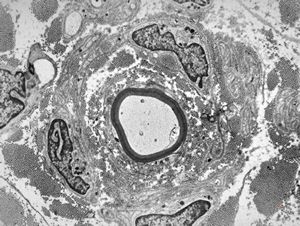

F,12y. | hypertrophic (onion bulb) neuropathy - n.suralis

F,12y. | hypertrophic (onion bulb) neuropathy - n.suralis

F,12y. | hypertrophic (onion bulb) neuropathy - n.suralis